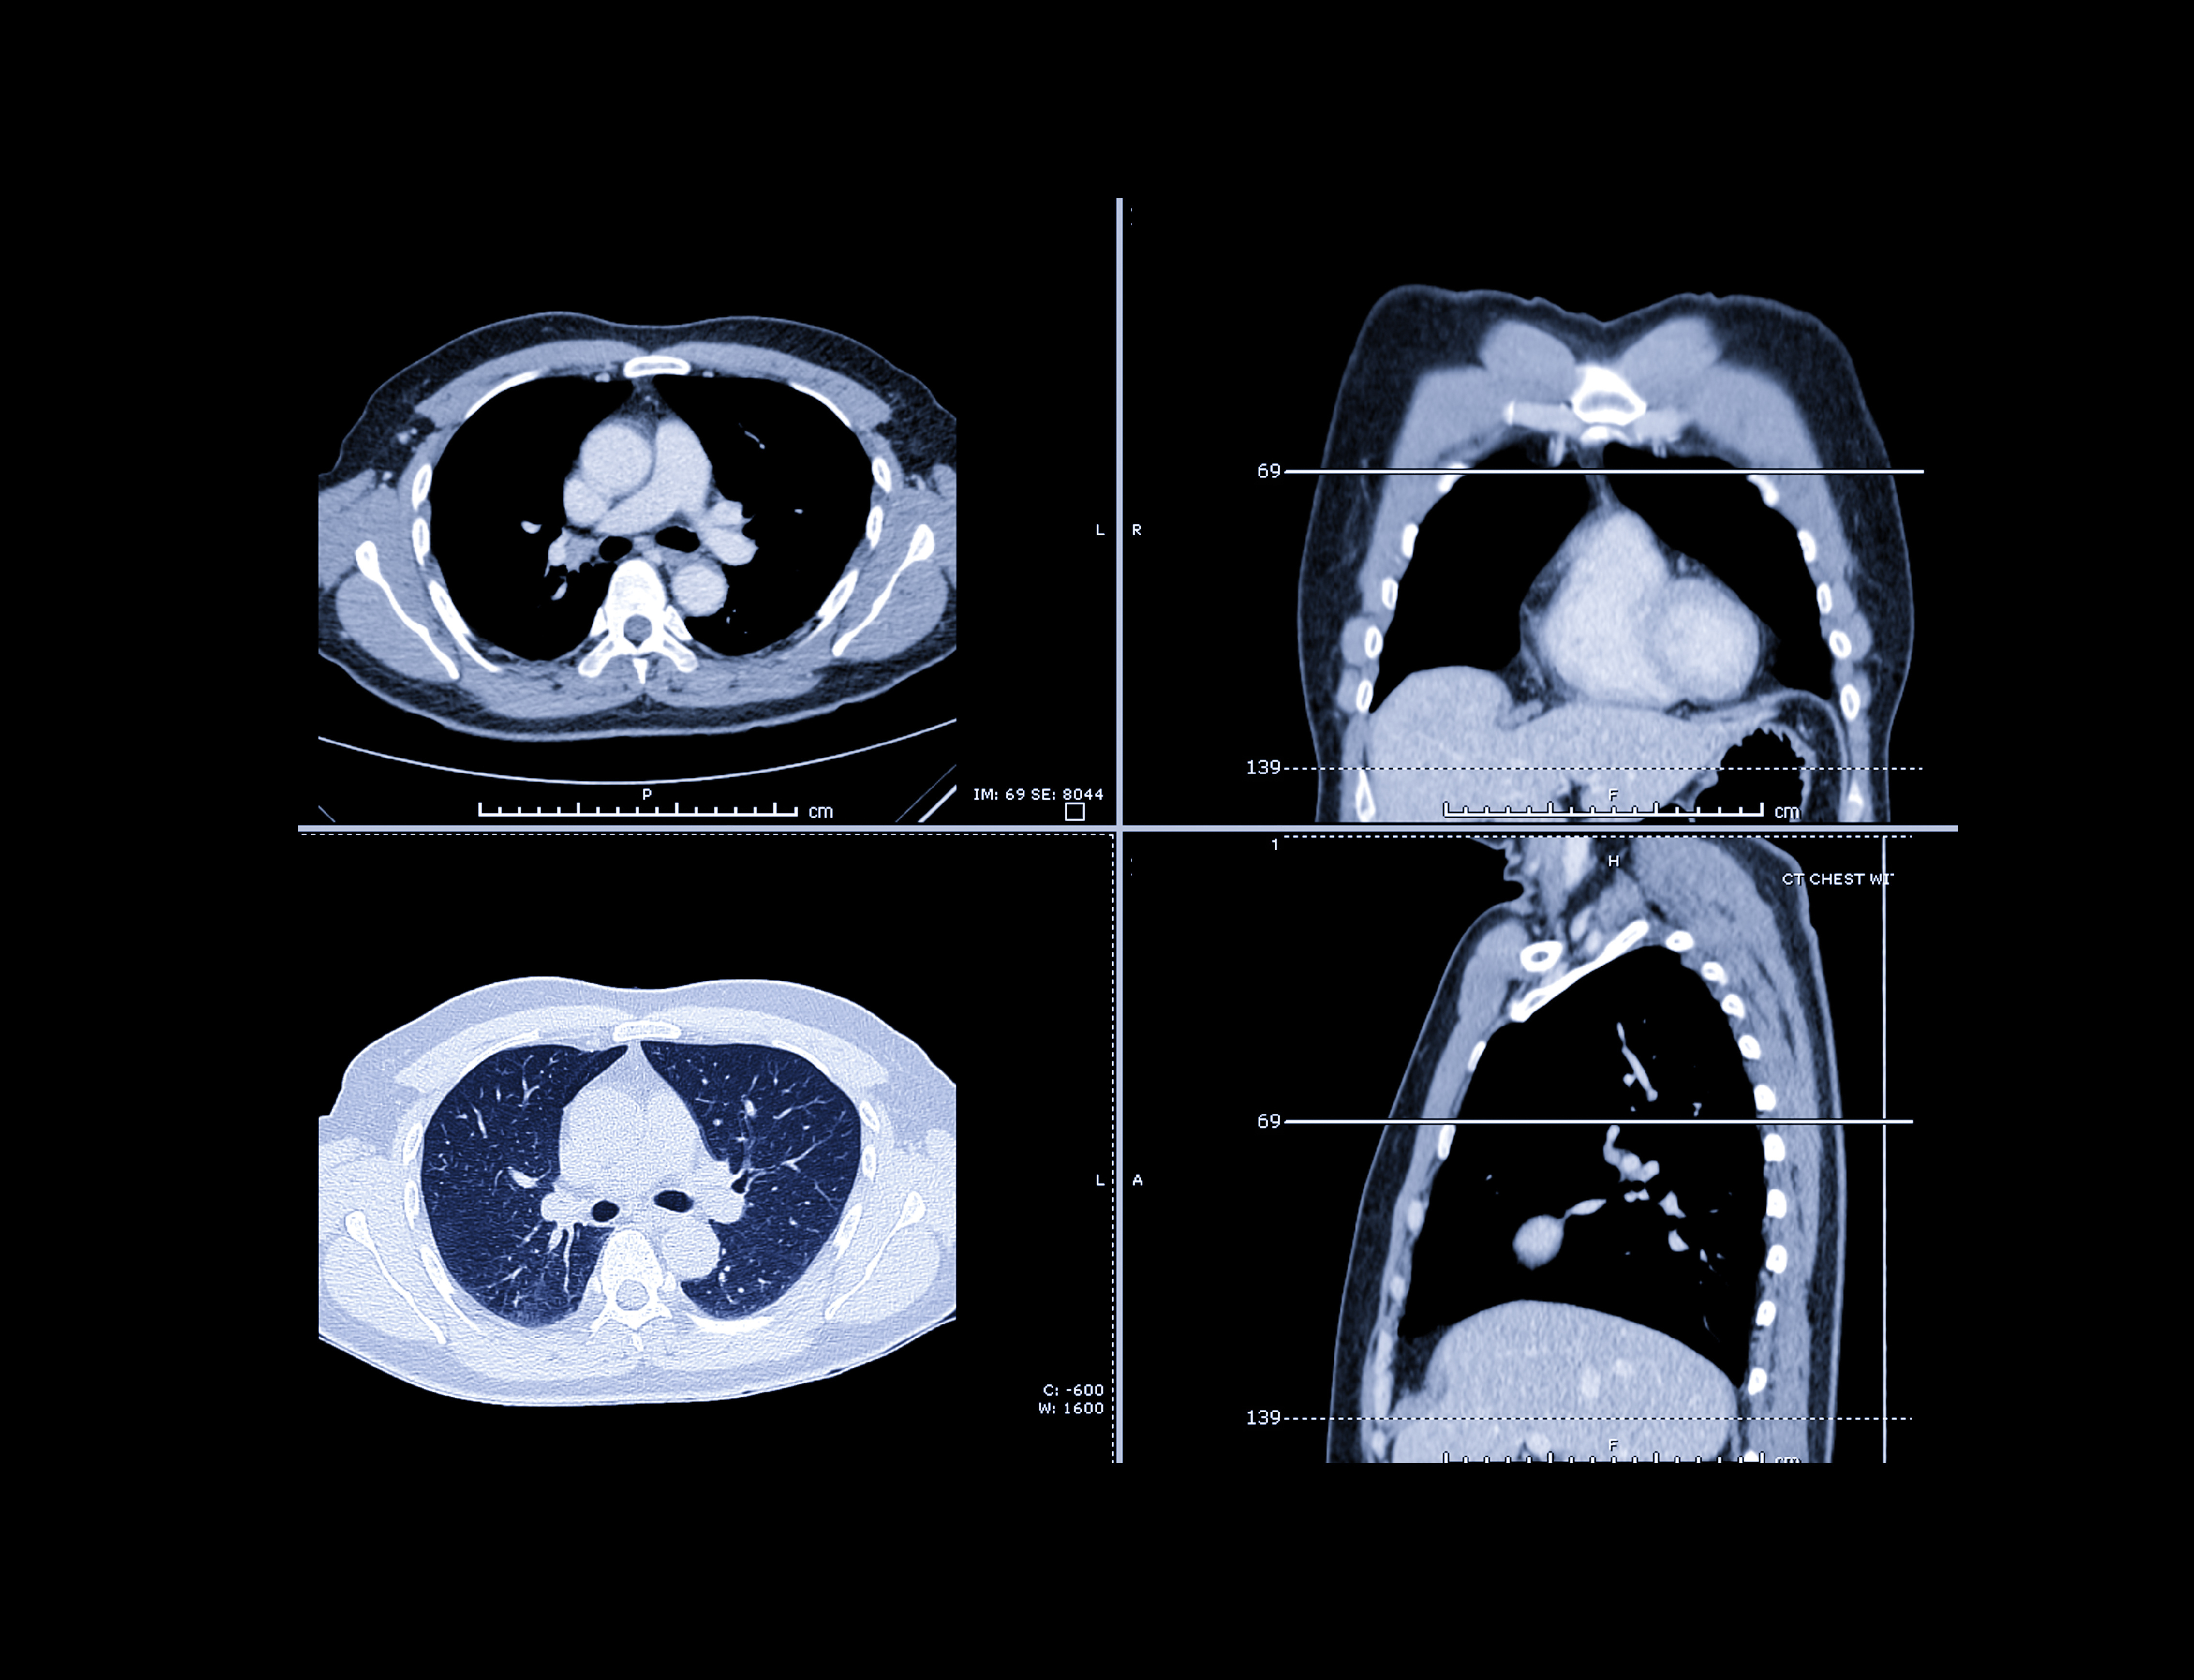

CT lung screening has been demonstrated to reduce mortality by 20% among high-risk individuals like heavy smokers. But much of the recent research into CT lung cancer screening has focused on racial and gender disparities in screening.

In the current study, a team led by Adriana Rodriguez Alvarez of Boston University wanted to focus more closely on gender disparities in CT lung screening. The group analyzed data from the Boston Lung Cancer Study acquired from 2013-2021. In all, 1,216 individuals diagnosed with lung cancer were included in their analysis; of these, 9.4% had undergone CT lung cancer screening.